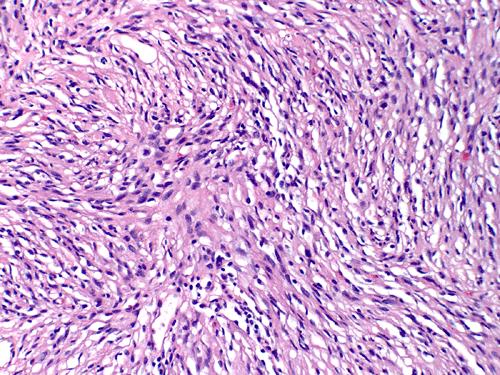

At low magnification, the lesion appears as a spindly, desmoplastic neoplasm with storiform arrangement that could be seen in some mesenchymal tumors (Panel A). On higher magnification, the overall pleomorphism is relatively mild. Mitotic figures are not readily seen. There are some round to triangular cells that are surrounded by a rim of retraction artifactual space from the surrounding desmoplastic component  (Ţ in Panel B). These cells seem like a drop of oil floating on water. The morphologic features of these cells are suggestive of ganglionic cells and/or gemistocytic astrocytes. In other areas, tumor cells containing melanin pigment (Panel C) are present. Deposition of reticulin material can be seen essentially around every single cells (Panel D). Scattered within the tumors are large ganglionic that can be well demonstrated by immunohistochemistry for synaptophysin (Panel E). Tumor cells with mature neuronal phenotype is also immunoreactive for NeuN (Panel F). Immunohistochemistry should that the amount of astrocytic cells far out numbered ganglionic cells (Panel G). Cells that express melanin are also strongly positive for HMB45 on immunohistochemistry.

Microscopically, the desmoplastic activity is so widespread that it would suggest sarcomas to the novices. Recognition of this potential pitfall is of importance during intraoperative consultations. DIA and DIG have known tendency to extend into the Vichow-Robin space. However, there is a typical, marked demarcation between the desmoplastic tumor and the cortex. Spindle cells arranged in fascicles, storiform, or wholed pattern intermixed with collagenous component are common findings and is particularly associated in areas with leptomeningeal involvement. On detailed examination, neoplastic  neuroepithelial cells with features of astrocytes, gemistocytic astrocytes, and neurons (ganglion cells) are common. It is very common that the gemistocytic astrocytes and ganglionic cells have a retraction, artifactual space at their cytoplasmic border. These large cells appear like drops of oil in water (i.e., the desmoplastic component). The collagenous component will stain blue and the neuroepithelial component will stain pink or red on Masson’s trichrome. A reticulin stain will show deposition of reticulin material around individual tumor cells. Significant nuclear pleomorphism is not a usual feature of these tumors. Mitosis is quite uncommon and the Ki-67 labeling index for cyclinc cells ranges from less than 0.5% to 5% 2. Necrosis and endothelial proliferation should not be seen. The glial component can be well demonstrated by immunohistochemistry for GFAP. The ganglionic component can be well demonstrated by immunohistochemistry for synaptophysin, neurofilament proteins, synaptophysin, NeuN, class III beta-tubulin and MAP2.